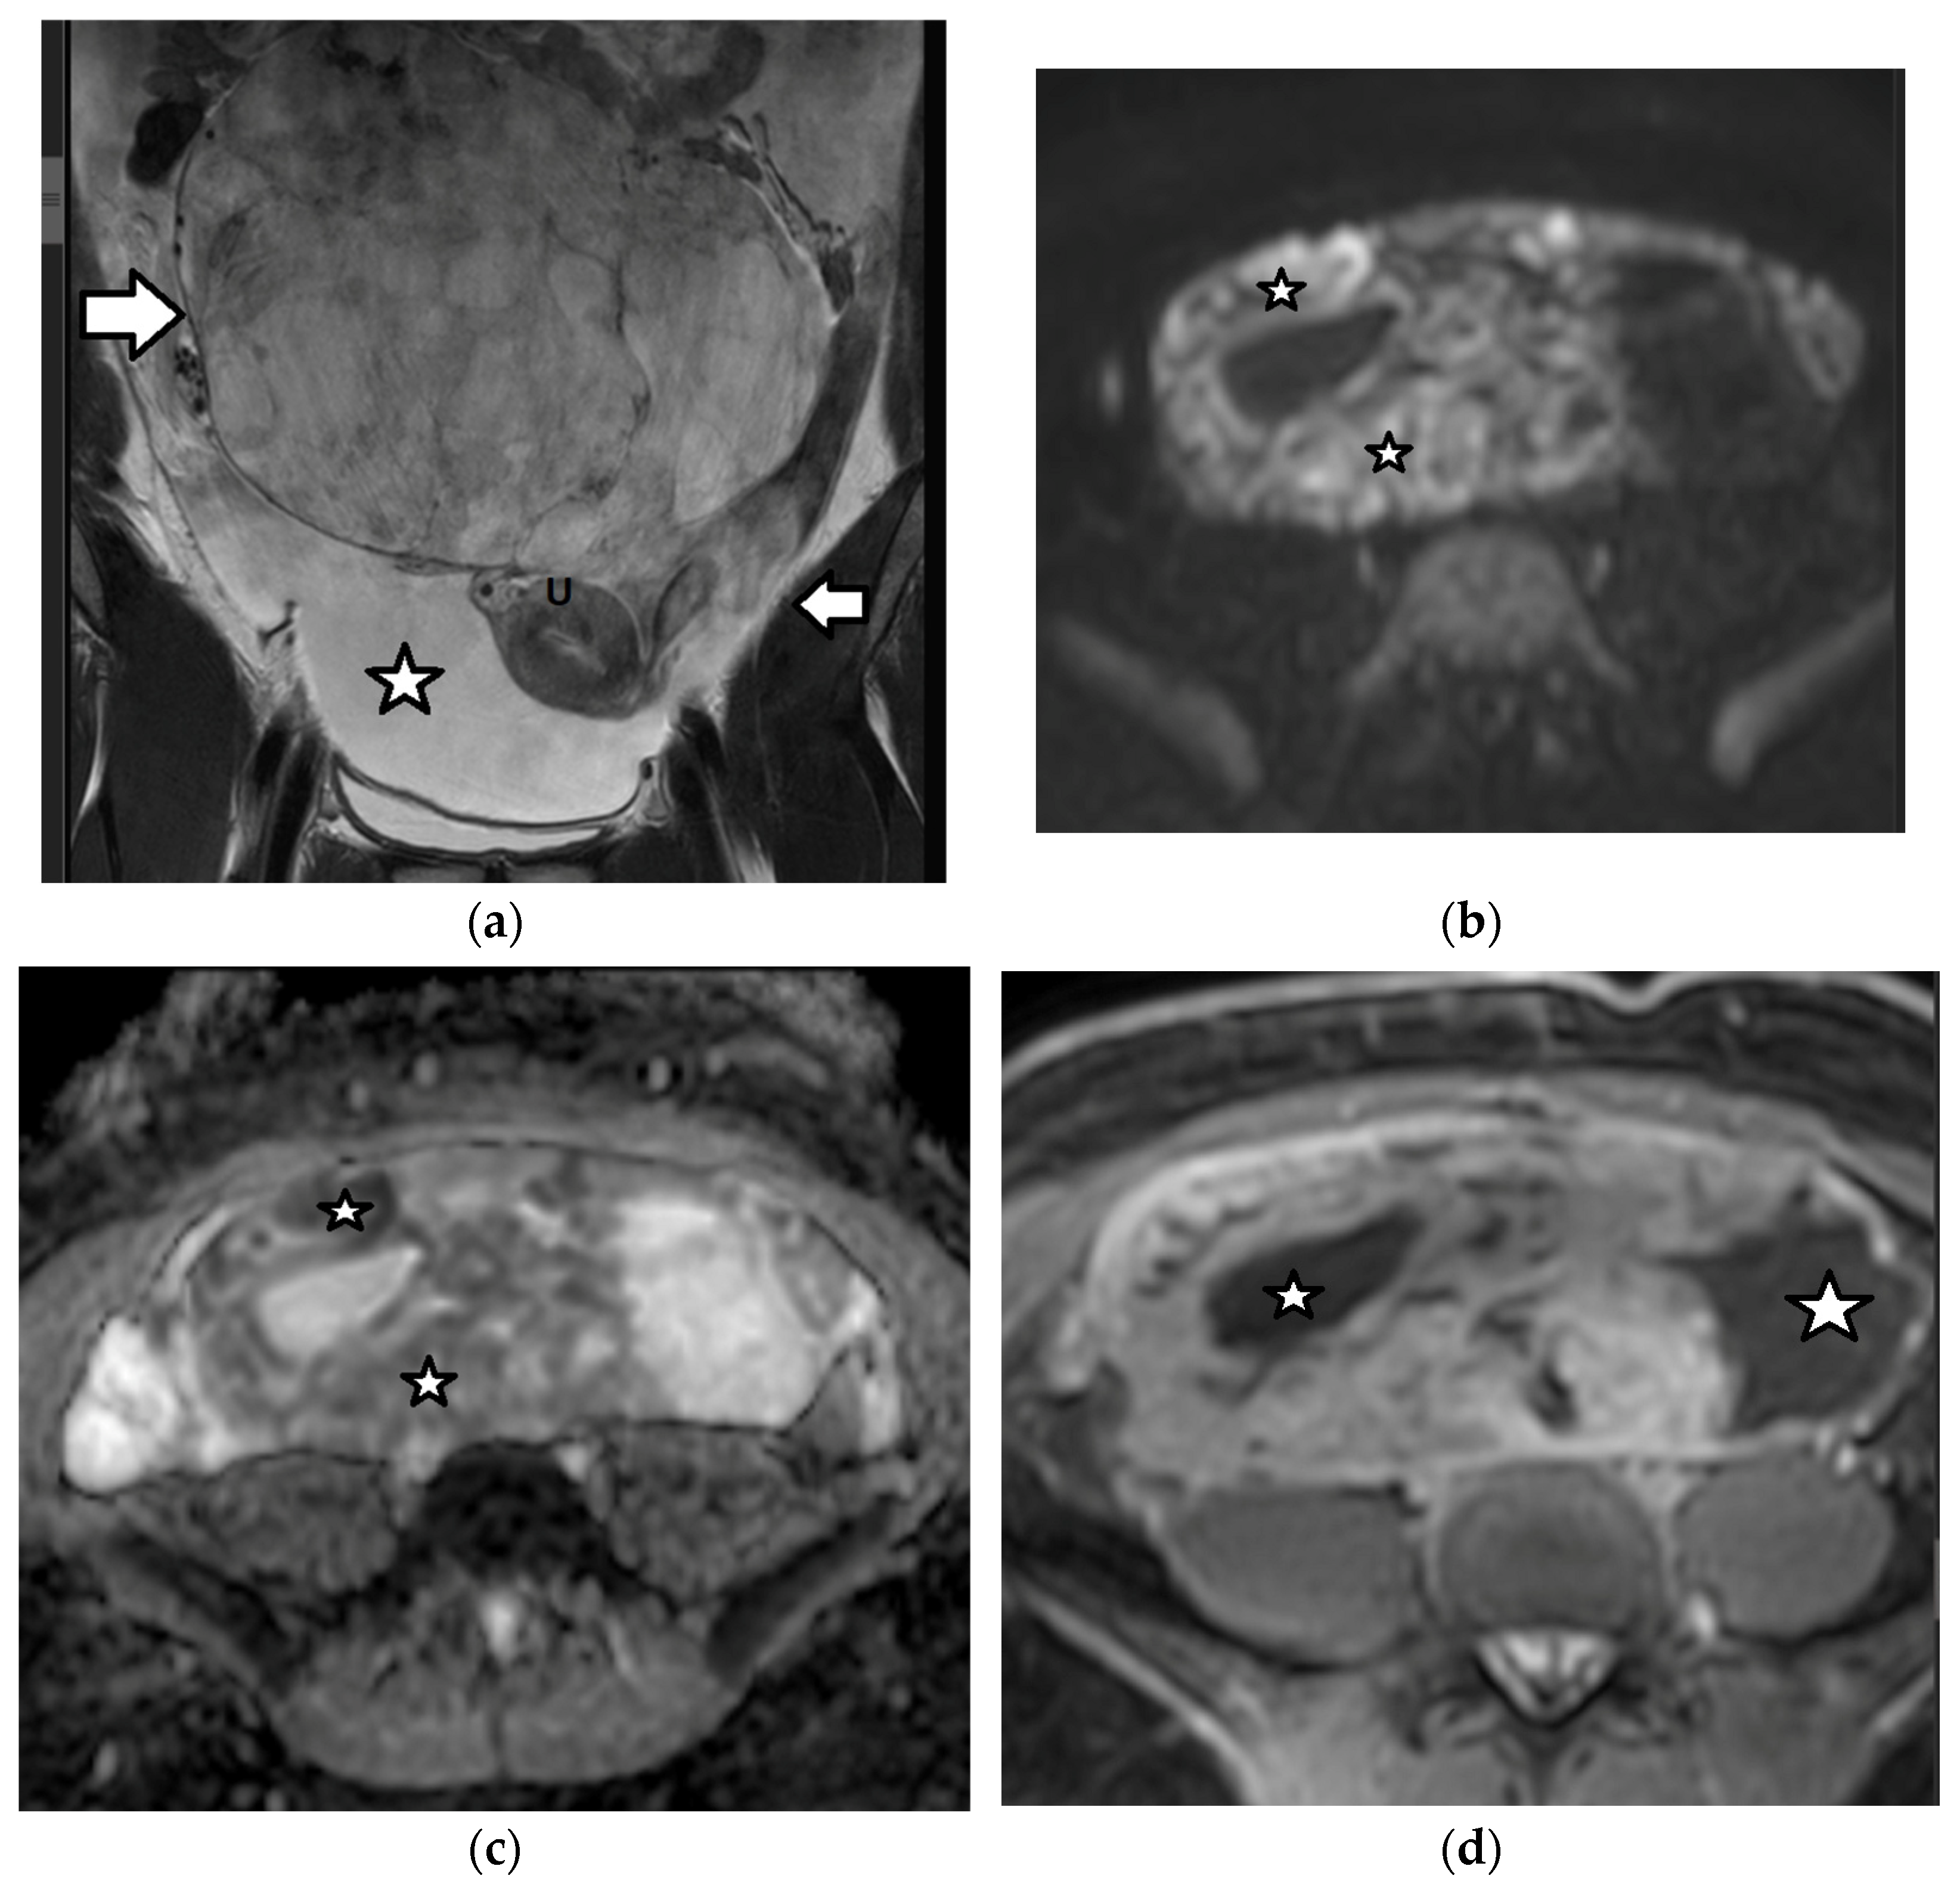

| Dysgerminoma | most common ovarian malignancy 30% of MOGCTs mean age: second, third decades; 10%: first decade bilateral: 10–15% associated with gonadal dysgenesis, gonadoblastoma, chromosomal abnormalities, e.g., Turner syndrome | often diagnosed at an early stage favorable prognosis involvement of pelvic or retroperitoneal lymph nodes recurrence: 13–20% | increased LDH: 95% increased β-hCG (syncytiotrophoblastic giant cells): 5% | large, well-defined, lobulated, mainly solid tumor fibrovascular septa: characteristic

|